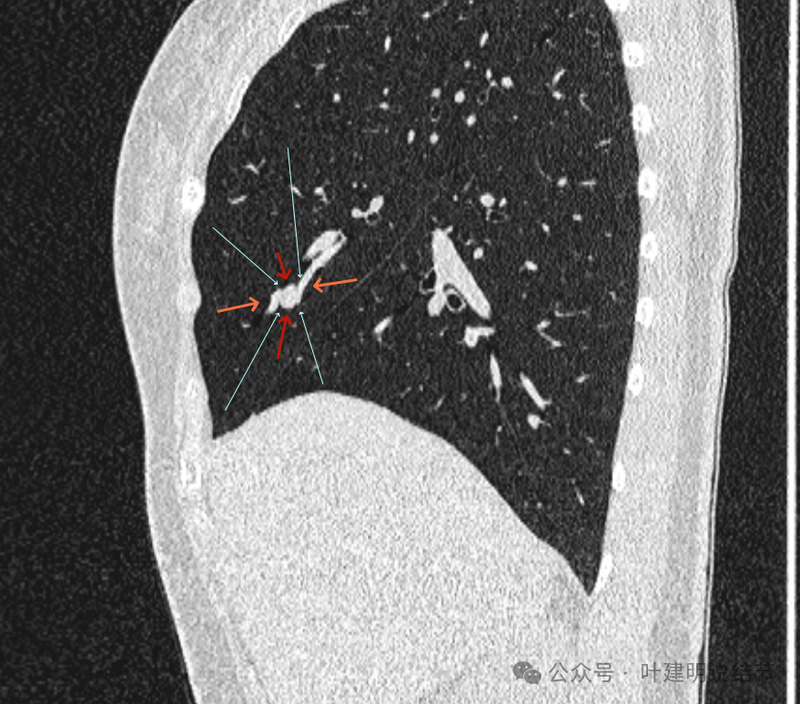

再看矢状位影像:

桔色的是血管,红色的是病灶,两者之间有间隙仍用天蓝色细线标注。

紧挨但仍有缝隙的。

血管贴着病灶,病灶表面略有毛糙之处。

血管有形成轻微血管弯征,两者紧贴。

两支血管夹着病灶,密度不同,有低密度间隙。

病灶与两侧血管关系均密切,明显觉得密度是不一样的,血管的密度略高,结节的略低。

病赤与血管在蓝色箭头处失去间隙,像是侵蚀血管壁,造成血管受侵犯破坏。病灶是软组织密度的,而且整体看有膨胀感。

病灶密度稍不均。表面不光滑。

病灶与边上血管间隙不清。

桔色箭头所示的血管受压稍有移位。

密度不同,关系密切。

边缘区域也是有膨胀感。

血管与病灶脱开后的样子。

边缘区也是基本上实性的。